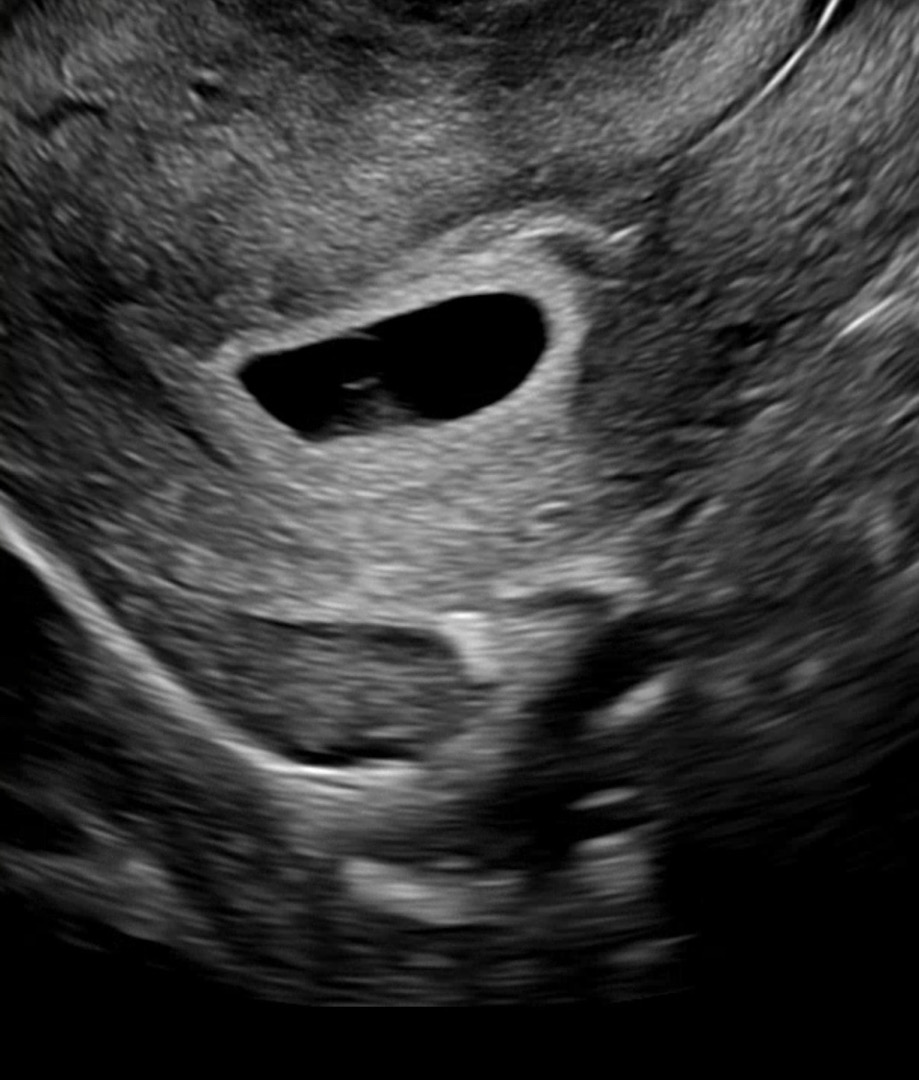

초음파 사진좀 봐주세용

오늘 5주5일인데, 5주0일에 출혈이슈 후에 아기집 찌그러졌고, 지금은 출혈x 피고임x 오늘 초음파에 난황이 너무 흐릿해서요! 처음 초음파봤을땐 난황 뚜렷햇거든요🥲

감사합니당..! 크기는 괜찮다고하셨는데, 너무 흐리네요 ㅠㅠ